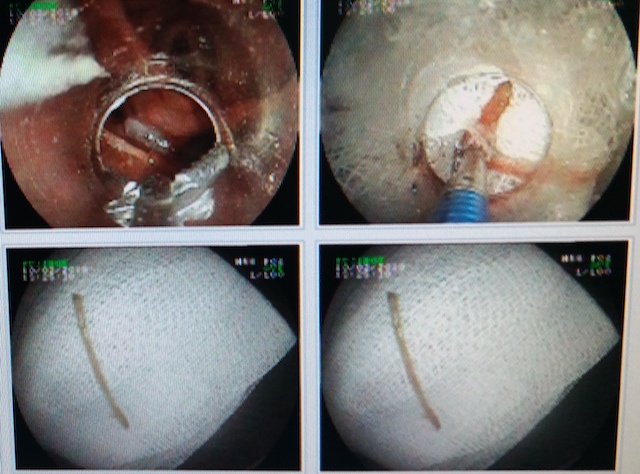

| Xương vịt dài 4 cm được bác sĩ nội soi gắp ra từ cổ họng bệnh nhân. Ảnh: Bệnh viện cung cấp. |

Khi nhập viện, bệnh nhân tỉnh, nuốt đau, khó nuốt, cảm giác nghẹn thở, sinh hiệu ổn. Bác sĩ đã chụp X quang vùng cổ, ngực thấy dị vật cản quan và chẩn đoán dị vật vùng cổ nghi hóc xương vịt sau ăn.

Các bác sĩ đã nội soi gắp dị vật là mảnh xương dài 4 cm. Sau gắp xương bệnh nhân khỏe, nuốt giảm đau, cảm giác dễ chịu. Mạch, huyết áp, hô hấp ổn định.